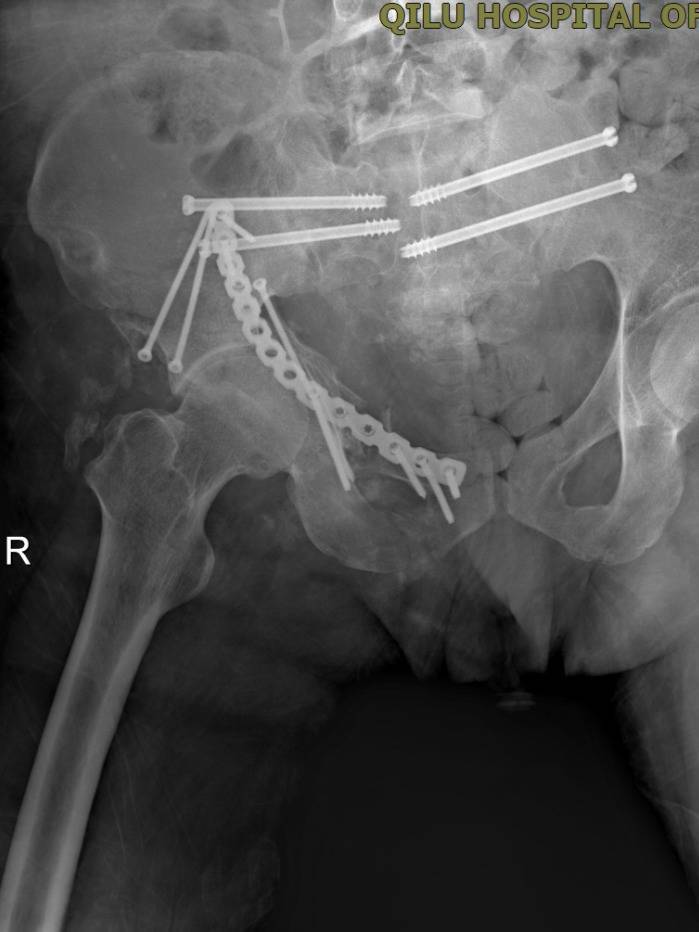

r3月13日,一场高难度的骨盆重建手术率先展开。因患者整个骶骨粉碎性骨折移位明显,血压和身体状况无法耐受开放性大手术,且患者骨性结构破坏严重,置钉极为困难。主刀医生刘涛主任反复调整、精细操作,最终成功置入4枚骶髂螺钉,固定稳定可靠,带领急诊外科团队成功完成了手术。

▲骨折终极固定术后复查影像。